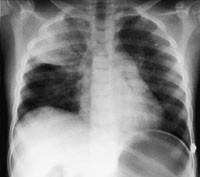

Røntgen thorax i serie med første bilde tatt to timer (fig 1) etter ekstubasjon viste fortetninger forenlig med interstitielt ødem og overlappsatelektase. Ødemet nærmest normaliserte seg i løpet av ni timer (fig 2) og fullstendig i løpet av 48 timer (fig 3), men med bestående atelektase. Pasienten var på dette tidspunkt helt ubesværet. Siste kontrollbilde tatt etter 14 dager var helt normalt.

Lungeødem som utvikles ved forsert inspirasjon har god prognose, men kan være assosiert med tilstander som i seg selv kan være livstruende. Det kliniske bildet varierer fra et fulminant lungeødem med blodtilblandet ekspektorat og klare røntgenfunn, til det mer vanlig forekommende moderate kliniske bildet med uklare røntgenfunn. Vår pasient hadde et moderat klinisk bilde, men røntgenbildene viste klare funn i form av en overlappsatelektase og interstitielt ødem (fig 1 – 3). All den tid pasienten var klinisk upåfallende før operasjonen og oksygeneringen var normal under operasjonen, tror vi lungeforandringene oppstod etter operasjonen. Overlappsatelektasen kan ha oppstått som en følge av det kraftige negative intrapleurale trykk under forsert inspirasjon, en trykkgradient som vil være maksimal mot lungetoppene hos en sittende eller stående pasient. Asymmetrien kan skyldes slimplugging. Derved er atelektasen et resultat av dynamisk lungekollaps som raskt reekspanderer spontant eller ved hjelp av CPAP-behandling. Tidlig bronchusavgang til høyre overlapp gjør denne sårbar for blokade av en tube som sitter like distalt for carina.